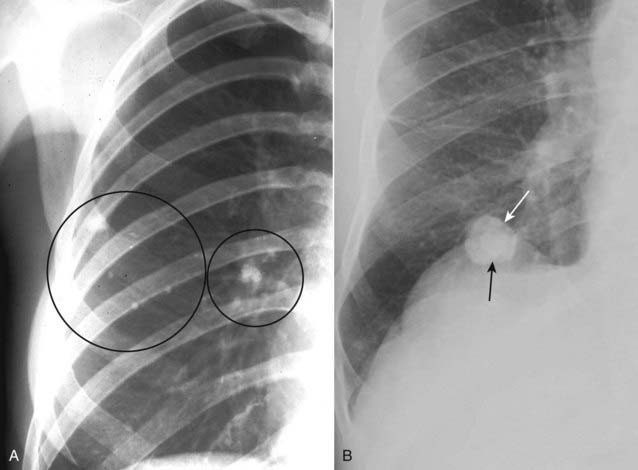

Figure 12-14 Calcified tuberculous granulomas and histoplasmoma.

When a pulmonary nodule is heavily calcified, it is almost always benign. A, Tuberculous granulomas are common sequelae of prior, usually subclinical, tuberculous infection and are usually homogeneously calcified (black circles). B, Histoplasmomas (solid white arrow) may contain a central or “target” calcification (solid black arrow) or may have a laminated calcification, which is diagnostic. CT can be used to differentiate between a calcified and a noncalcified pulmonary nodule with greater sensitivity than conventional radiographs.